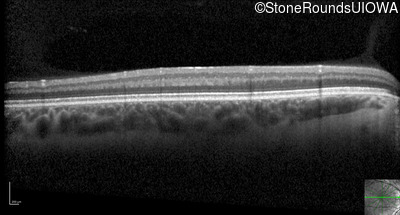

Optical Coherence Tomography - Right - 10/160 +1 sc

Exemplar / OCT Stack

Optical Coherence Tomography - Left - 10/200 sc